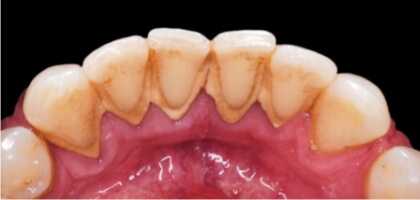

Mantenemos tu la salud bucodental al día, previniendo la aparición de enfermedades. Eliminaremos el sarro que se acumula en las encías o el cuello de nuestros dientes y las manchas, realzando la estética general con una sonrisa limpia, sana y agradable.